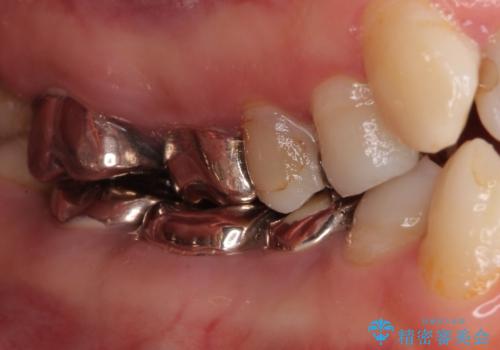

- 全顎的な歯列不正と、銀歯だらけの奥歯を気にして来院された患者様です。

奥歯の銀歯は、セラミッククラウンを装着するには歯の高さが不十分であり、そのままでは矯正治療を行うことが困難であるため、歯冠長延長術を行うこととしました。

また、根管治療の必要な歯がいくつかあるため、歯周外科治療の治癒期間を利用して根管治療を行い、その後インビザラインにて矯正治療を行うこととしました。